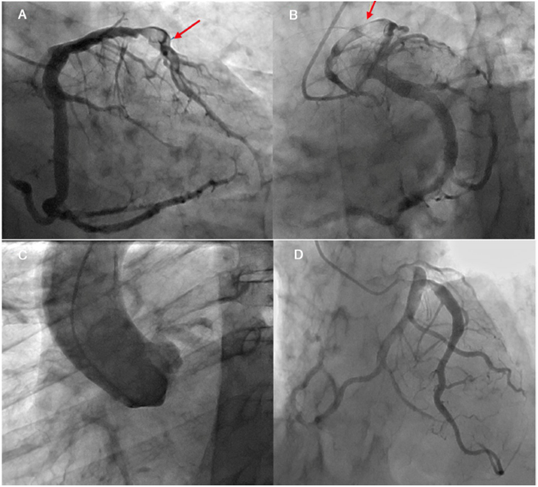

Paciente de 78 años, de sexo masculino, quien cursó con infarto agudo al miocardio con elevación del ST no trombolizado de 24 horas de evolución, clínicamente definido como Killip I y sin angina postinfarto. Como antecedentes patológicos refirió artritis reumatoide y cáncer de próstata en manejo con hormonoterapia. El ecocardiograma transtorácico mostró ventrículo izquierdo de tamaño normal, con disquinesia apical FEVI de 45%. El electrocardiograma evidenció bloqueo AV de primer grado, onda Q patológica en pared inferior y trastorno de la repolarización generalizado; eje desviado a la izquierda. Se llevó a angiografía coronaria en la que se halló tronco angiográficamente normal; arteria descendente anterior: tipo III, gran trombo intraluminal en el tercio medio del vaso y flujo TIMI I (fig. 3); arteria circunfleja: vaso dominante, de gran calibre, con ectasia; coronaria derecha con origen anómalo, la cual se encuentra sin lesiones obstructivas.

Figura 3 A. Arteria descendente anterior con trombo en tercio medio (flecha). Se observa ectasia de la arteria circunfleja. B y C. Arteria descendente anterior con trombo en el tercio medio (flecha). Ectasia de arteria circunfleja originando arteria coronaria derecha. En aortograma no se observa ostium de la coronaria derecha ya que nace de la arteria circunfleja. D. Control a las ocho semanas. Se observa ectasia de la arteria descendente anterior en tercio proximal y medio (resolución total de trombo). Origen anómalo de arteria coronaria derecha.

A los 4 días se realizó revisión angiográfica en la cual se documentó disminución del trombo y se manejó finalmente con rivaroxabán 2,5 mg cada 12 horas, ácido acetil salicílico (ASA) 100 mg día y clopidogrel 75 mg día.

A las ocho semanas se hizo un nuevo control angiográfico en el que se halló tronco: angiográficamente normal; arteria descendente anterior: tipo III, ectasia en su tercio proximal y medio, con resolución total de la carga de trombo y flujo distal del vaso TIMI III Y TIMI conteo 41; arteria circunfleja: vaso de gran calibre, sin evidencia de lesiones obstructivas y originándose de este vaso la coronaria derecha, la cual se observa libre de lesiones obstructivas.